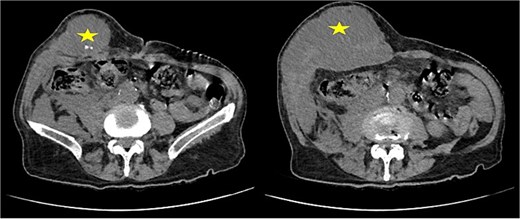

Abdominal ultrasound revealed a heterogeneous parietal collection with internal hyperechoic foci. A contrast-enhanced computed tomography (CT) scan confirmed a large abscess (9 × 12 cm) within the abdominal wall, extending posteriorly, containing multiple calcified foci consistent with gallstones (Fig. 2). No biliary dilation or intra-abdominal collection was detected.

Contrast-enhanced CT scan of the abdominal wall showing a parietal abscess containing hyperdense foci consistent with retained gallstones (star).